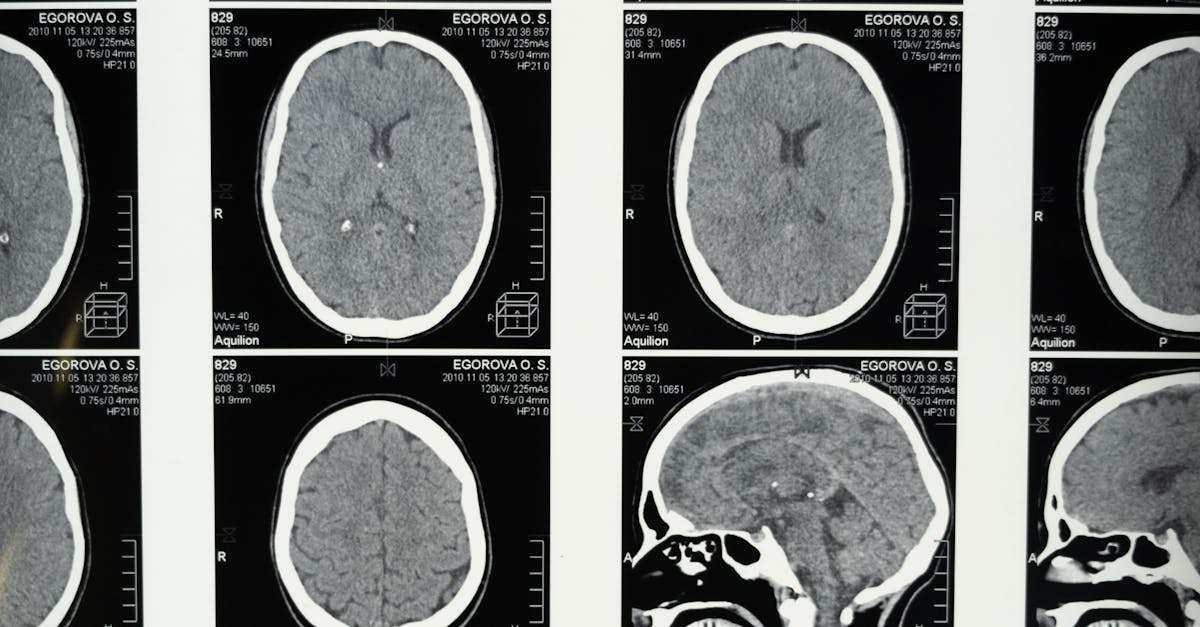

12 Neurological Conditions with Overlapping Symptoms

The human nervous system, with its intricate network of billions of neurons, presents one of medicine's most challenging diagnostic frontiers when dysfunction occurs. Neurological conditions often share remarkably similar symptom profiles, creating a complex web of overlapping presentations that can confound even the most experienced clinicians. From the tremors that characterize both Parkinson's disease and essential tremor to the cognitive decline seen in Alzheimer's disease and frontotemporal dementia, the boundaries between distinct neurological disorders frequently blur. This diagnostic complexity stems from the interconnected nature of neural pathways, where damage to different regions can produce surprisingly similar clinical manifestations. The challenge is further compounded by the fact that many neurological conditions progress gradually, with early symptoms often being subtle and nonspecific. Understanding these overlapping presentations is crucial for healthcare providers, patients, and families navigating the diagnostic process, as accurate identification can significantly impact treatment strategies, prognosis, and quality of life outcomes.